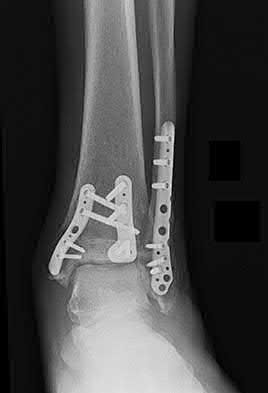

Question 19

A 28-year-old male sustains a closed comminuted tibial shaft fracture.

Two hours post-injury, he develops severe leg pain unyielding to narcotics. His blood pressure is 120/80 mmHg. Intracompartmental pressure monitoring is performed. Based on current guidelines, which measurement dictates an emergent 4-compartment fasciotomy?

Explanation

Acute compartment syndrome is classically defined by tissue hypoperfusion. The absolute compartment pressure is less reliable than the differential pressure (Delta P). A Delta P (Diastolic Blood Pressure minus Compartment Pressure) of less than 30 mmHg is an absolute indication for emergency fasciotomy, as capillary perfusion gradient is lost when tissue pressure approaches the diastolic pressure.